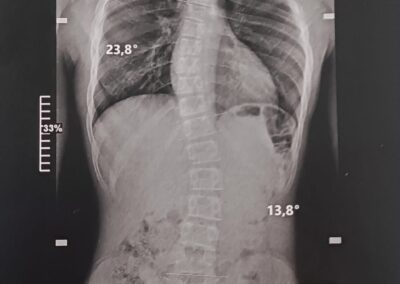

La scoliose est une déviation de la colonne vertébrale dans les 3 plans de l’espace. Celle-ci amène une silhouette asymétrique (visible au niveau des épaules et de la taille) et l’apparition de gibbosités (bosse), ainsi qu’un déséquilibre et une limitation de mouvement du tronc. Dans certains cas graves, la capacité respiratoire du patient peut se trouver limitée.

Le traitement se fait par appareillage au moyen d’un corset orthopédique sur mesure, moulé sur le corps et conçu de manière à permettre une croissance normale du rachis en corrigeant les déformations existantes.

Chaque corset est réalisé et adapté selon la morphologie du patient. Il tient compte de la déformation du rachis, du poids et de la taille de celui-ci, ainsi que de la prescription médicale. Selon la déformation du rachis et le modèle de corset prescrit, les temps de port de ce dernier peuvent être variables. De même des ajustements peuvent être réalisés selon l’évolution de la pathologie et de la morphologie du patient.